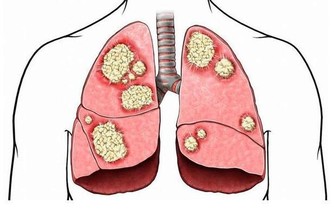

***4、下肢動脈硬化、閉塞***

患有心腦血管病、高血壓、高血脂、糖尿病者,當出現下肢酸痛、腿抽筋、行走不便等症狀時,應該想到是否有動脈硬化、狹窄或閉塞。